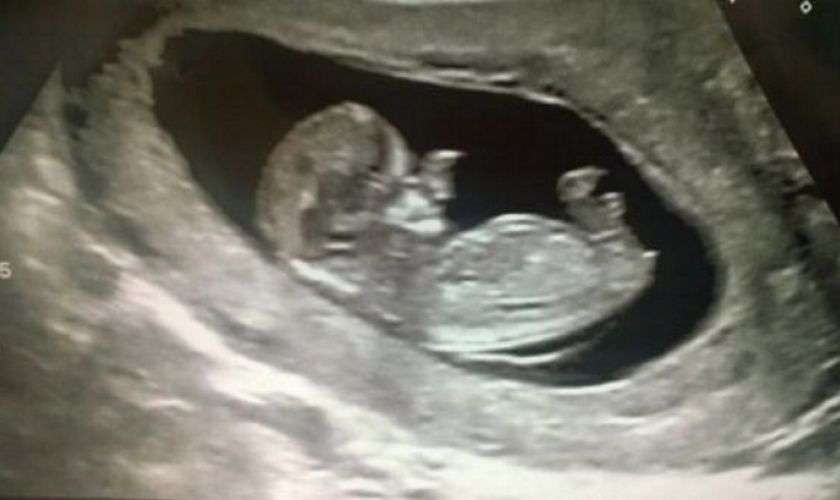

Правда, на 20-й неделе беременности врачи, делая УЗИ, обнаружили, что вокруг носа сына Эми растут дополнительные мягкие ткани. Тогда женщина впервые узнала, что ее сын родится не таким, как все.